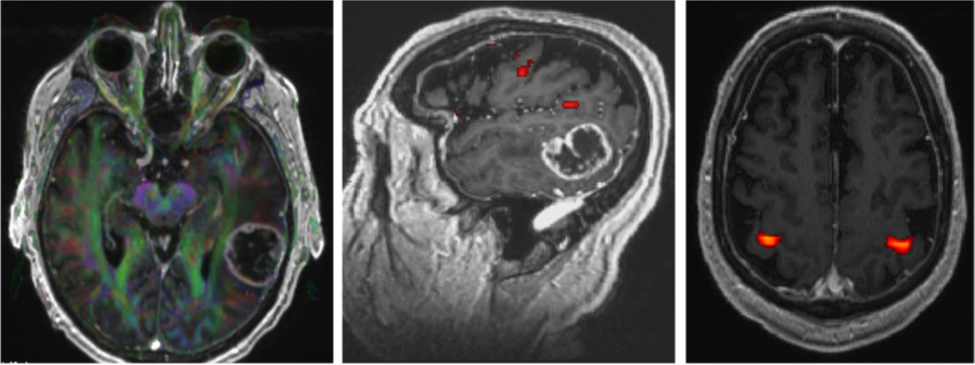

Phim MRI chức năng đóng vai trò quan trọng khi làm xét nghiệm cho bệnh nhân bị u nguyên bào thần kinh đệm, mục đích để xác định các vùng vỏ não chức năng quan trọng và mối tương quan của chúng với u (hình 2). Thông tin về mối liên quan này sẽ giúp quá trình bóc u được hiệu quả và an toàn. Ở hình 2, bệnh nhân có khối u nguyên bào thần kinh đệm lớn ở thái dương trái. MRI chức năng cho thấy vùng ngôn ngữ tiếp nhận (vùng Wernicke) nằm ngay cạnh khối u ở bờ sau của thùy thái dương trên.

Hình 2. MRI chức năng xác định các dãi chất trắng (hình bên trái), vùng ngôn ngữ (hình giữa) và vùng vận động của tay (hình bên phải).

Phương pháp tốt nhất cho bệnh nhân này là phẫu thuật mở sọ tỉnh (awake craniotomy) để xác định vùng vỏ não phụ trách chức năng nói, nhờ đó phẫu thuật viên có thể lấy bỏ được tối đa khối u và giảm thiểu nguy cơ bị rối loạn ngôn ngữ vĩnh viễn. Trong quá trình phẫu thuật tỉnh, bệnh nhân được yêu cầu thực hiện một loạt các nhiệm vụ thần kinh liên quan đến lời nói trong khi bác sĩ phẫu thuật kích thích não bằng một đầu dò điện. Khu vực phụ trách lời nói quan trọng được xác định sẽ không bị cắt bỏ, ngay cả khi khối u thâm nhiễm vào các khu vực này.